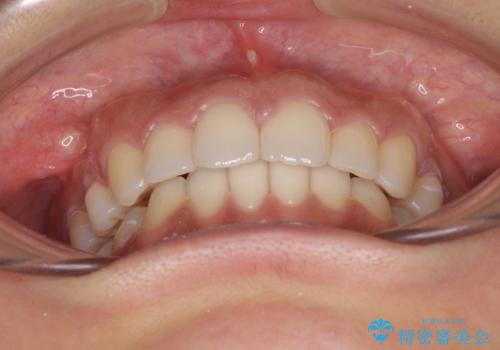

毎日22時間の装着時間を守ってくださいましたが、ハイペースにマウスピースを交換することなく、慎重に治療を進めてくださったので、治療期間はやや長くなりました。

臼歯部も含め、叢生が綺麗に改善され、患者様には大変満足していただきました。